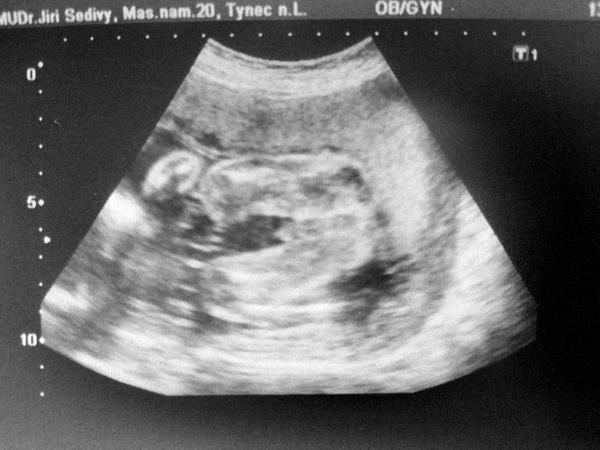

@monca531 taky čekáme druhého kluka a taky jsem věřila v holku, pan doktor mě vyvedl z omylu hned na prvnim screenu 🤣

@andullena jasný kuk